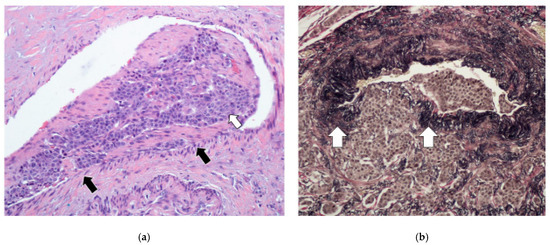

3.2. Mesenteric Fibrogenesis and Extramural Vascular Invasion

3.3. Tumor Infiltration Pattern